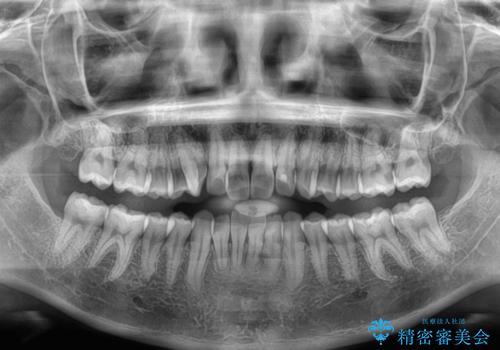

- 上下前歯のデコボコを気にして来院された患者様です。

ワイヤー矯正でもマウスピース矯正でも可能でしたが、短期間で、自身の手を煩わせることなく治療を行いたいとのことで、ワイヤー装置にて矯正治療を行うこととしました。

僅か8ヶ月という短期間で、綺麗な歯列に仕上がりました。